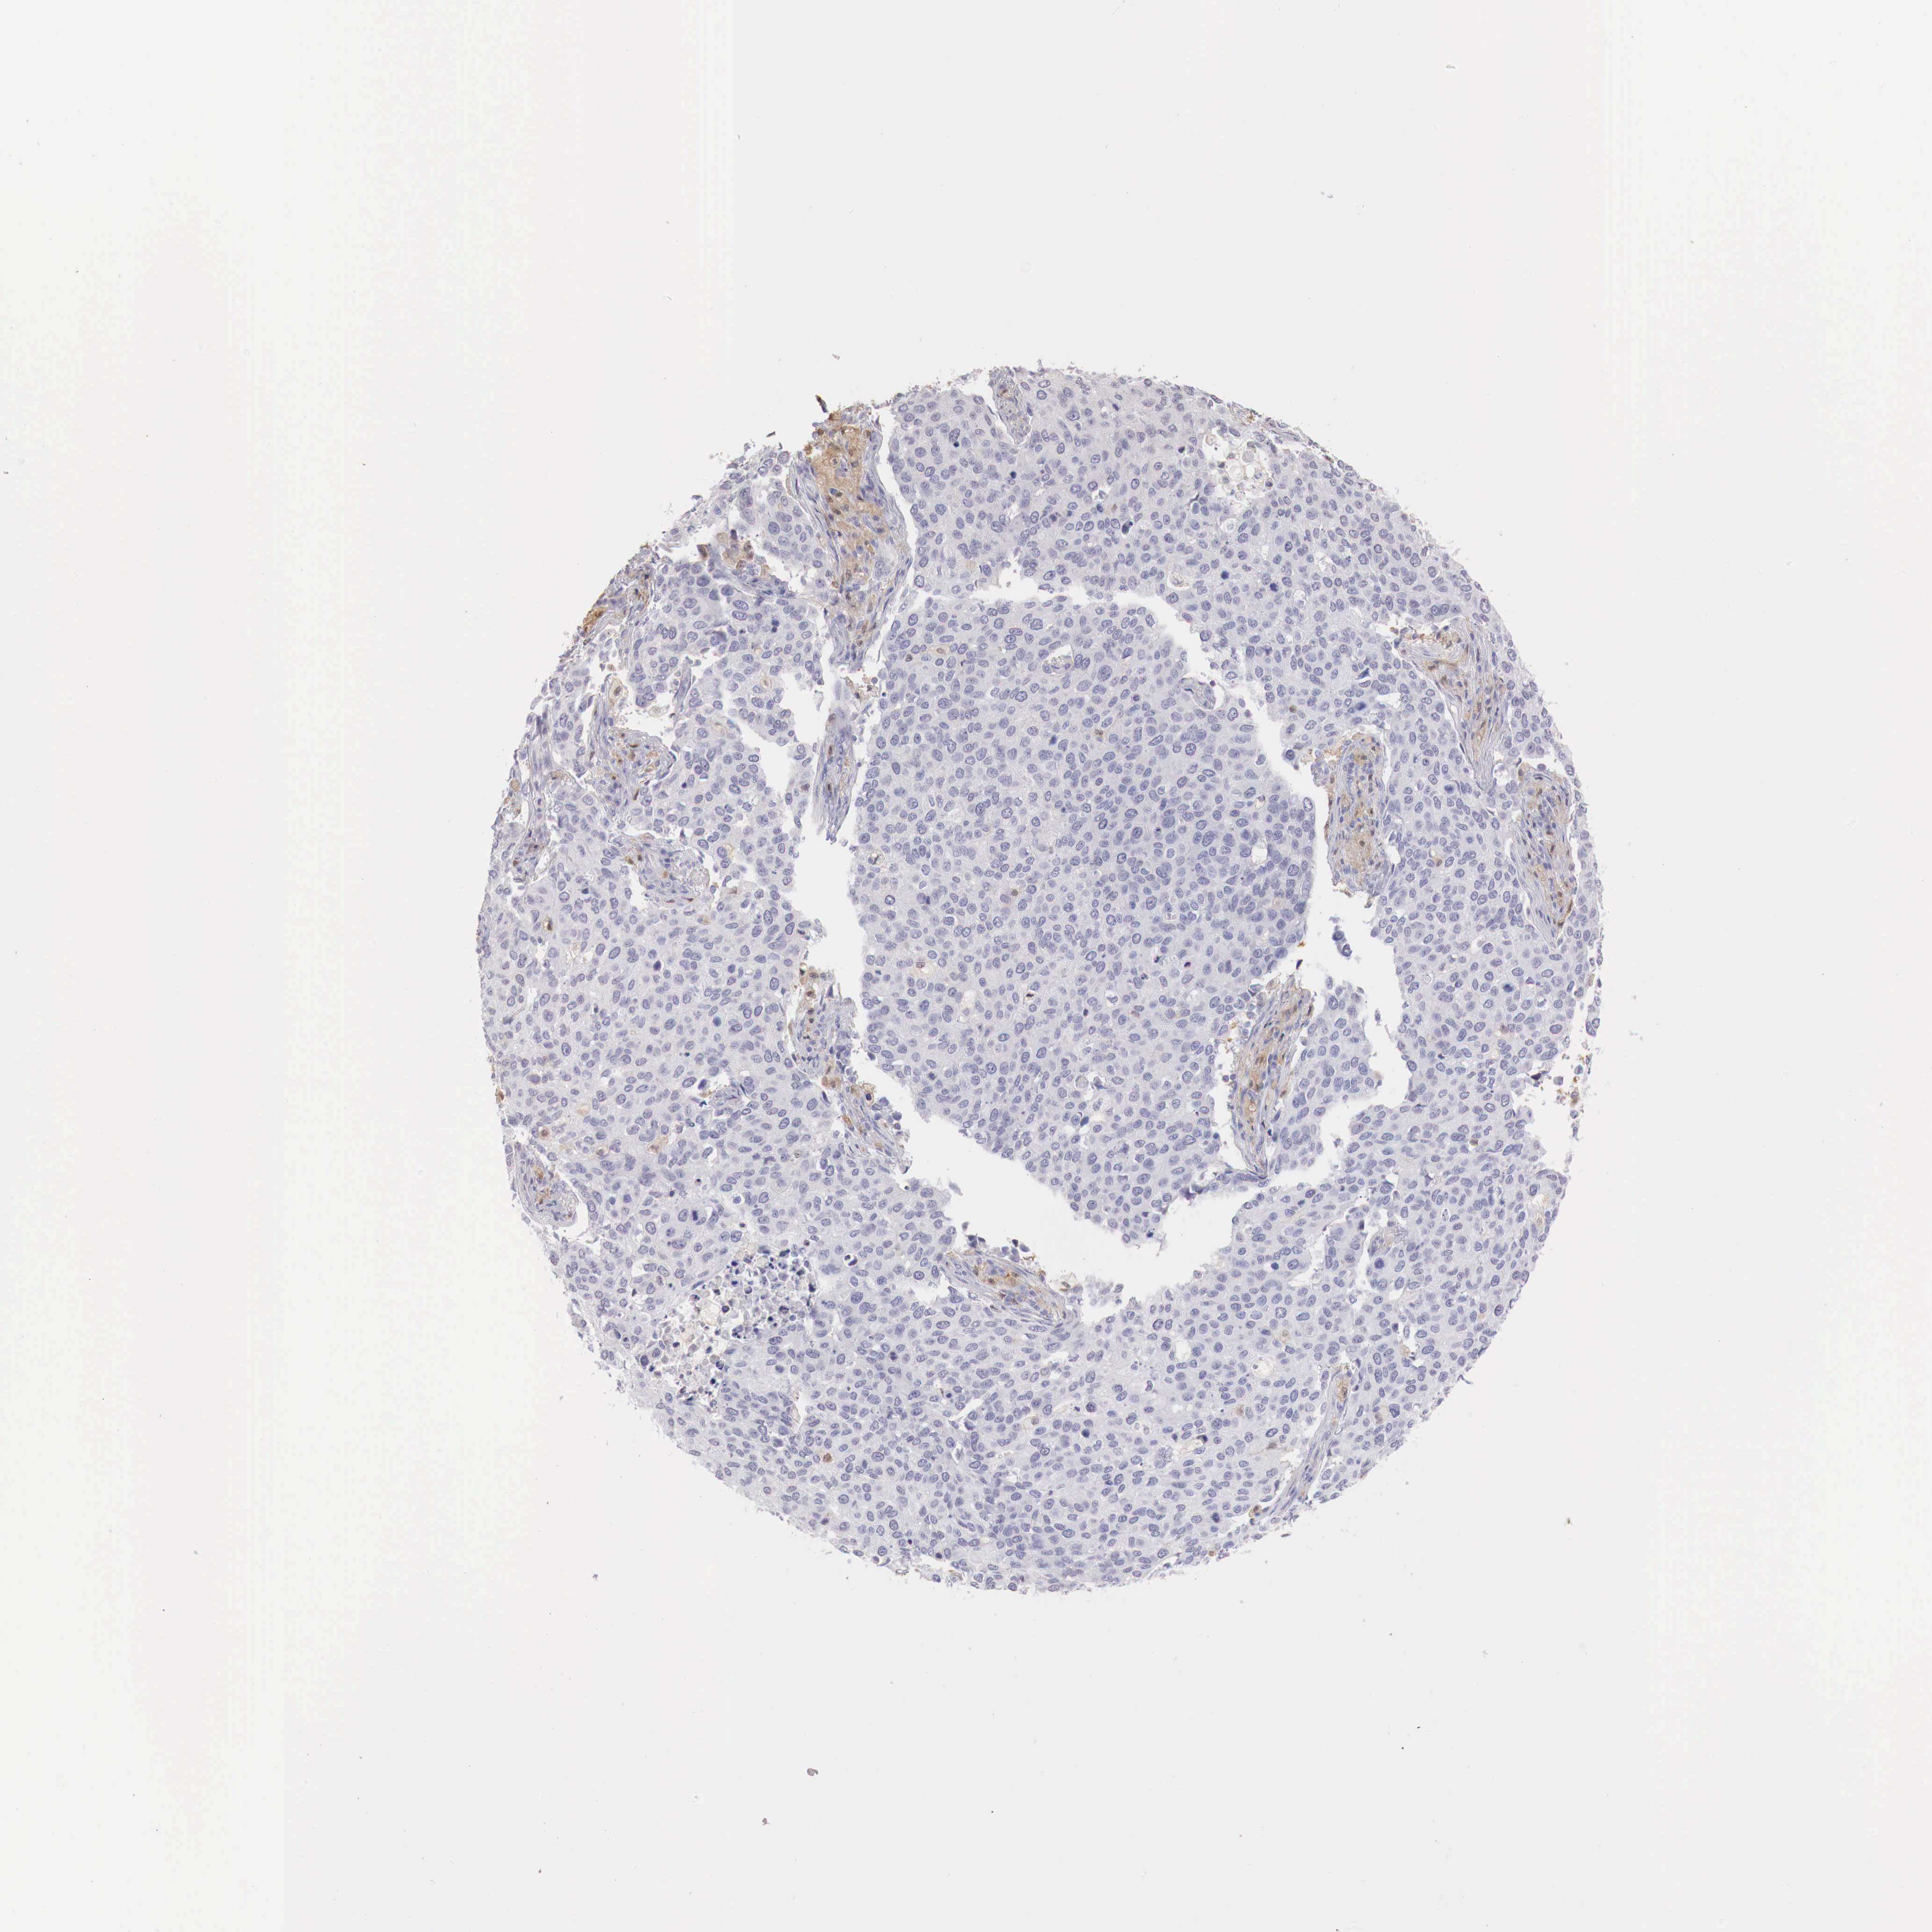

CERVICAL CANCER - Protein expressioni

A mouse-over function shows sample information and annotation data. Click on an image to view it in a full screen mode. Samples can be filtered based on level of antibody staining by selecting one or several of the following categories: high, medium, low and not detected. The assay and annotation is described here.

Note that samples used for immunohistochemistry by the Human Protein Atlas do not correspond to samples in the TCGA dataset.

Antibody stainingi

Antibody staining in the annotated cell types in the current human tissue is reported as not detected, low, medium, or high, based on conventional immunohistochemistry profiling in selected tissues. This score is based on the combination of the staining intensity and fraction of stained cells.

Each image is clickable and will lead to virtual microscopy that enables deeper exploration of all samples and also displays staining intensity scores, fraction scores and subcellular localization as well as patient and tissue information for each sample.

Antibody HPA000428

Antibody HPA000522

Staining

High

Medium

Low

Not detected

Intensity

Strong

Moderate

Weak

Negative

Quantity

>75%

75%-25%

<25%

None

Location

Nuclear

Cytoplasmic/membranous

Cytoplasmic/membranous,nuclear

Adenocarcinoma, NOS

Squamous cell carcinoma, NOS